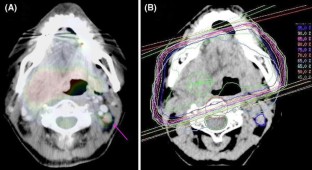

Fig. 2